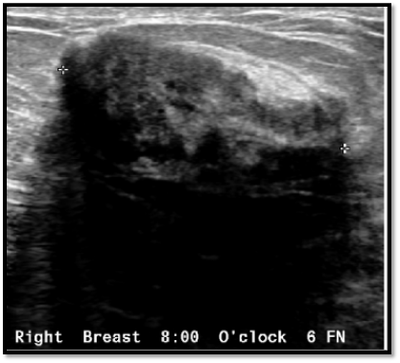

38 year old lady with right breast lump of one year duration.

What is the next step in the investigation?